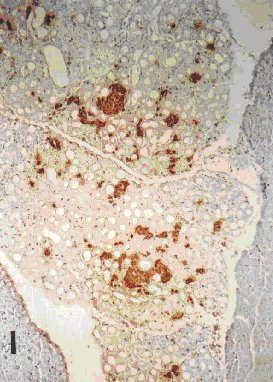

Near total acinar deletion was achieved by day three in four of the six animals, and total deletion by day 3½ (Figures 2 and 3) post duct ligation in all but one animal. Acinar deletion was accompanied by the replacement of the space, previously occupied by acinar tissue, with circular/spheroid structures of varying size (10-40 µm in diameter) and frequency (3-6 per 1000 µm2 ) in all experimental groups.

Figure 2. Day 3½ post PDL pancreatic tissue. ICC stained for insulin. x100. Bar = 100 µm. |

Figure 3. Day 3½ post PDL pancreatic tissue. ICC stained for glucagon. x100. Bar = 100 µm. |

Figure 2. Day 3½ post PDL pancreatic tissue. ICC stained for insulin. x100. Bar = 100 µm.

Figure 3. Day 3½ post PDL pancreatic tissue. ICC stained for glucagon. x100. Bar = 100 µm.